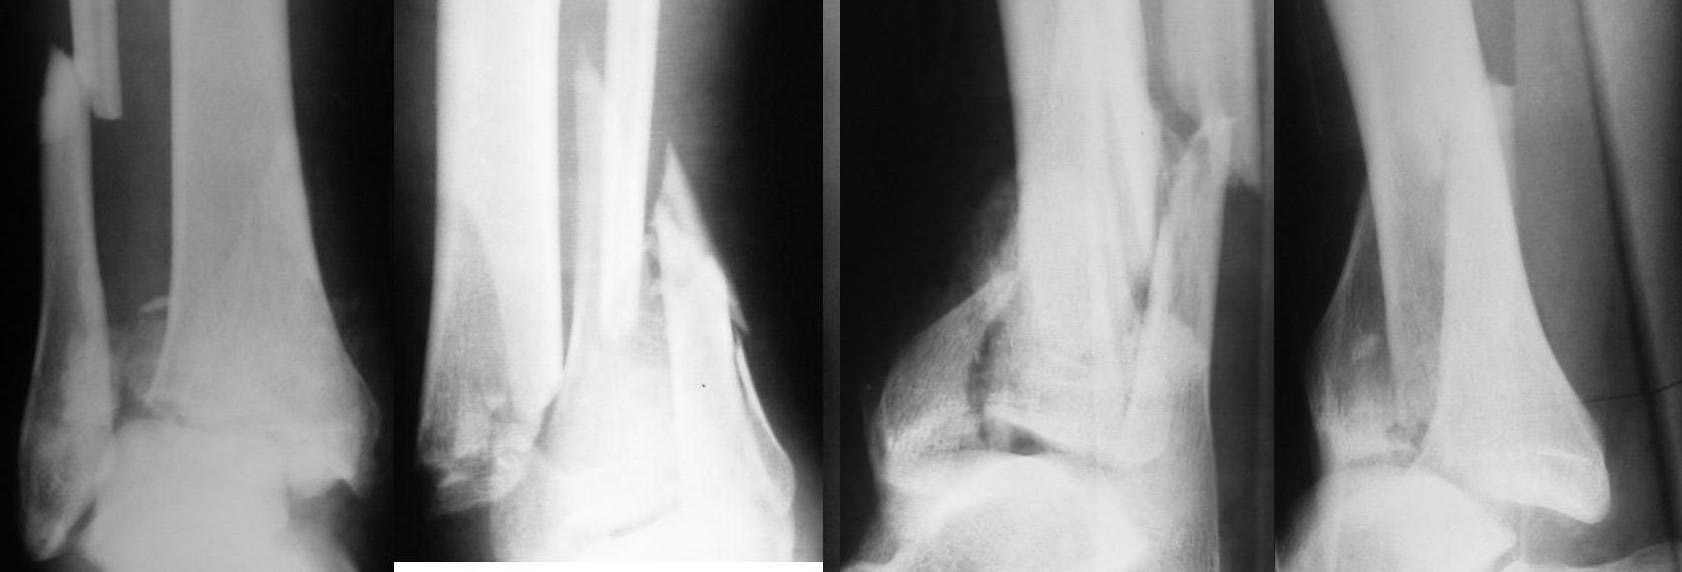

Больной 38 лет, поступил в отделение 13.01.2008г. Падение с высоты. Сложные переломы костей обеих голеней. Переломы - закрытые. Наложены гипсовые лонгеты. Какова дальнейшая тактика? Вид оперативного вмешательства?

( боюсь быть неточным в русских формулировках) - я бы фиксировал обе фибули пластинами; из небольших разрезов отдельными шурупами и спицами собрал бы, насколько возможно, дистальный отделы большеберцовых костей, потом наложил бы стержневые аппараты в нейтральном положении стоп ( на ходшую ногу можно слегка дать дистракцию, лучшую( правый снимок), возможно , удасться стабильно зафиксировать и без аппарата вообще, чисто погружным синтезом)

Мой нынешний consultant предложил бы первичнфй артродез худшего ( снимок слева) голеностопа блокированным гвоздем - врядли у этого сустава хорошие перспективы, первичный артродез может сэкономить больному многие месяцы жизни.

Простите, а вы уверены, что переломы закрытые?

Глядя на rtg в этом начинаешь сомневаться. И они находятся в лонгетах без репозиции? Да там уже кожи не должно остаться. Такие переломы оперировать желательно сразу при поступлении, в крайнем случае - на 2-й день и в этом случае необходима репозиция со скелетным вытяжением. Вид операции - накостный остеосинтез пластинками, шурупами, как кожа позволит.